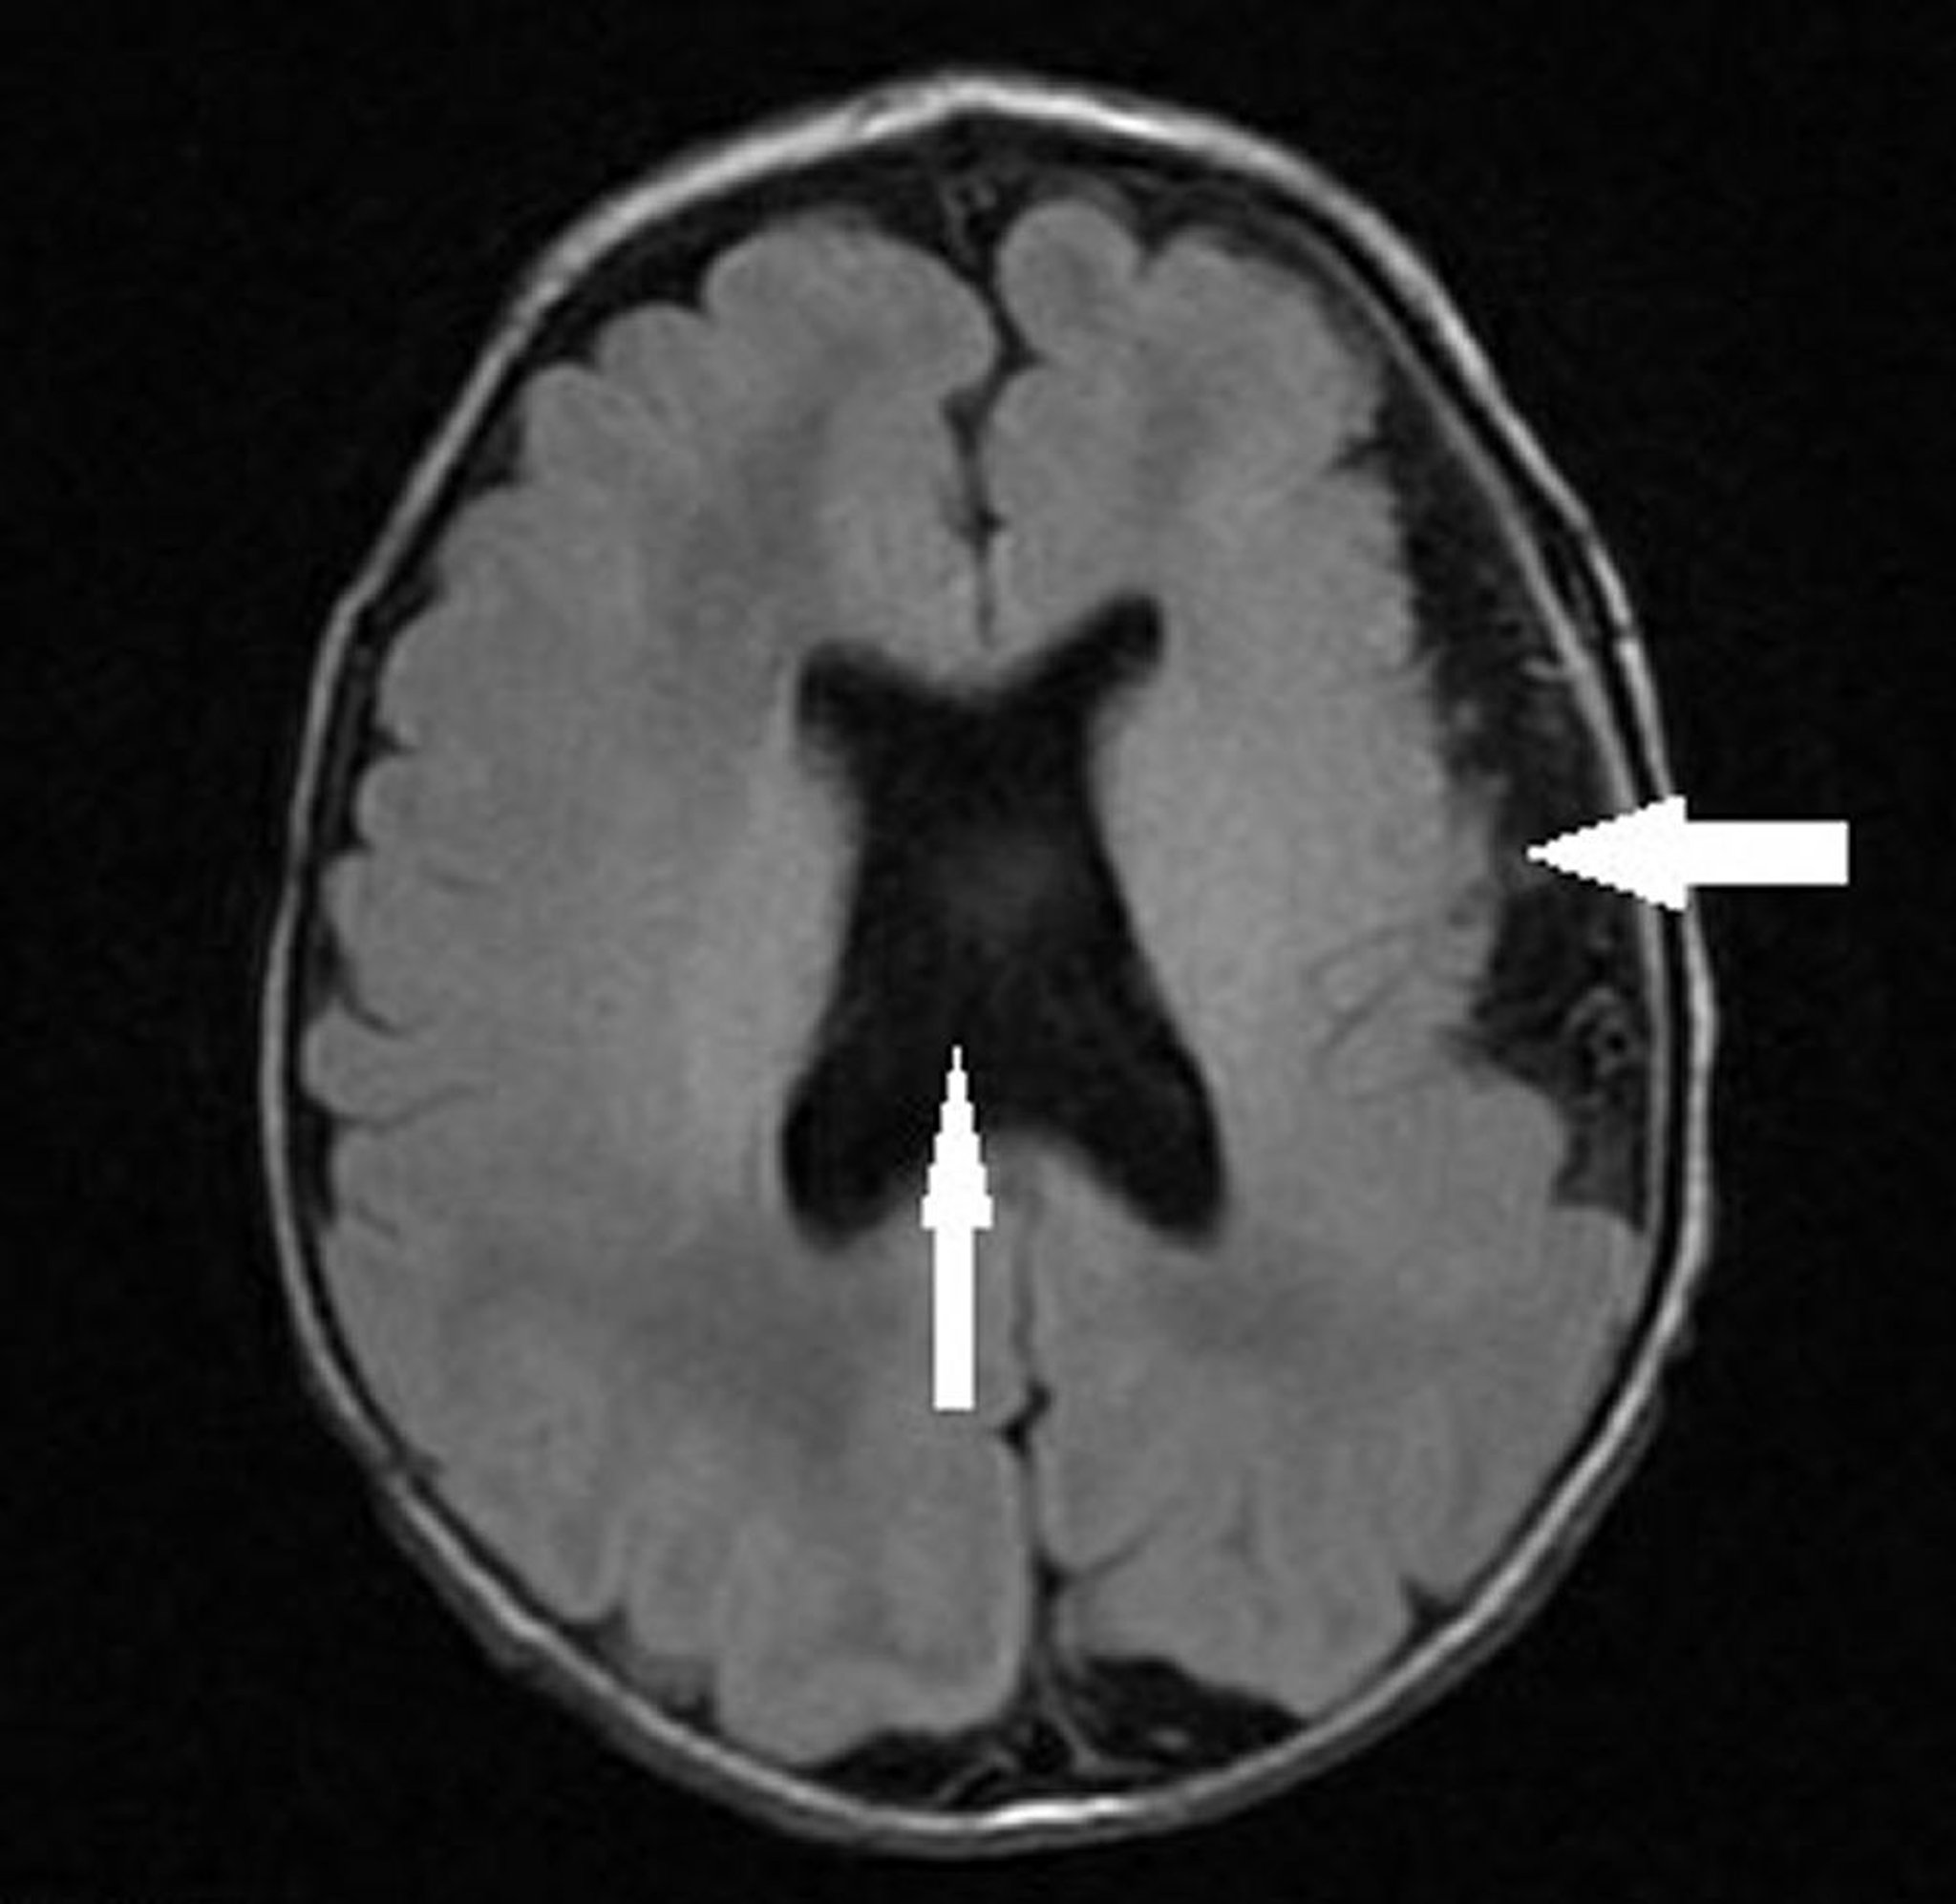

Dieses Abbild zeigt einen Säugling mit linkshemisphärischer Polymikrogyrie (Pfeil nach links) und fehlendem Septum pellucidum mit abnormaler Ventrikelkonfiguration (vertikaler Pfeil), die mit einer septo-optischen Dysplasie (Hypoplasie des Sehnervs, fehlendes oder abnormales Septum pellucidum und Hypophysenhypoplasie) einhergeht.

Image courtesy of Stephen J. Falchek, MD.